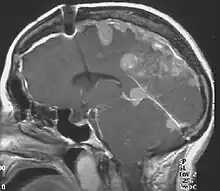

Neurofibromatosis type II (also known as MISME syndrome – multiple inherited schwannomas, meningiomas, and ependymomas) is a genetic condition that may be inherited or may arise spontaneously. The main manifestation of the condition is the development of bilateral benign brain tumors in the nerve sheath of the cranial nerve VIII, which is the "auditory-vestibular nerve" that transmits sensory information from the inner ear to the brain. Besides, other benign brain and spinal tumors occur. Symptoms depend on the presence, localisation and growth of the tumor(s). Many people with this condition also experience vision problems. Neurofibromatosis type II (NF2 or NF II) is caused by mutations of the "Merlin" gene,[2] which seems to influence the form and movement of cells. The principal treatments consist of neurosurgical removal of the tumors and surgical treatment of the eye lesions. Historically the underlying disorder has not had any therapy due to the cell function caused by the genetic mutation.

- Bilateral vestibular schwannoma (VS) or family history of NF2 plus Unilateral VS or any two of: meningioma, glioma, neurofibroma, schwannoma, posterior subcapsular lenticular opacities

- Unilateral VS plus any two of meningioma, glioma, neurofibroma, schwannoma, posterior subcapsular lenticular opacities

- Two or more meningioma plus unilateral VS or any two of glioma, schwannoma and cataract.